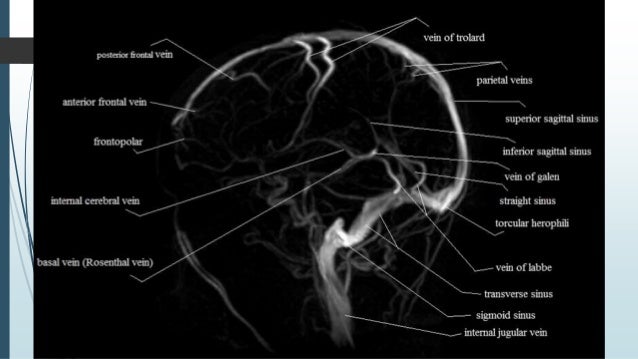

Dural Venous Sinus Thrombosis For Radiology & Imaging

sinus dural venous thrombosis vein labbe trolard